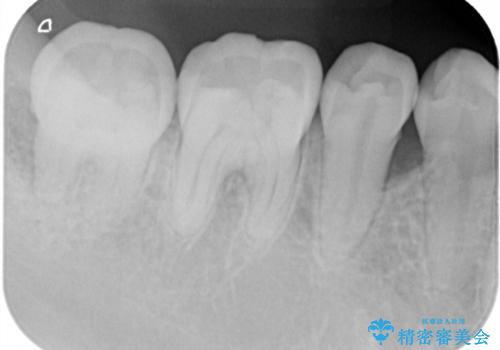

患者様は、他院で右下の歯を抜歯かもと言われました。全体の歯周病はなく、右下の1歯だけ骨が極端に減少していました(初診時歯周ポケット7mm。通常は3mm以下。)。その歯だけ咬合が強いことが原因と考えられたため、咬合を弱くする処置と減少した骨を再生する処置が必要になりました。

骨の再生治療手術をして10か月経過観察をしたのち、骨を平坦化する手術を行い、治療終了となりました。